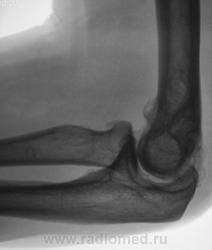

Пациент направлен на рентгенографию локтевого сустава. Была травма или не была не помнит. Пациент весьма пьющий, направлен хирургом с диагнозом "перелом". Рука в локтевом суставе полность не разгибается.

Ваше мнение уважаемые коллеги?

Наверно, застарелый перелом в области блока плечевой кости. Не понятен периостит.